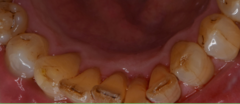

「上の前歯のデコボコを治したい」このような相談は、非常に多いです。